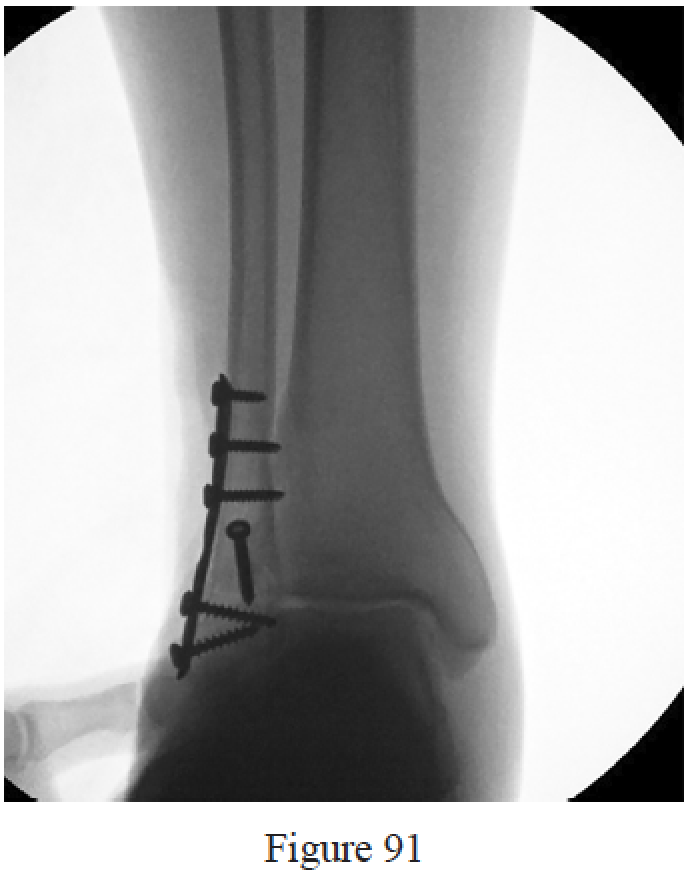

PREFERRED RESPONSE: 3